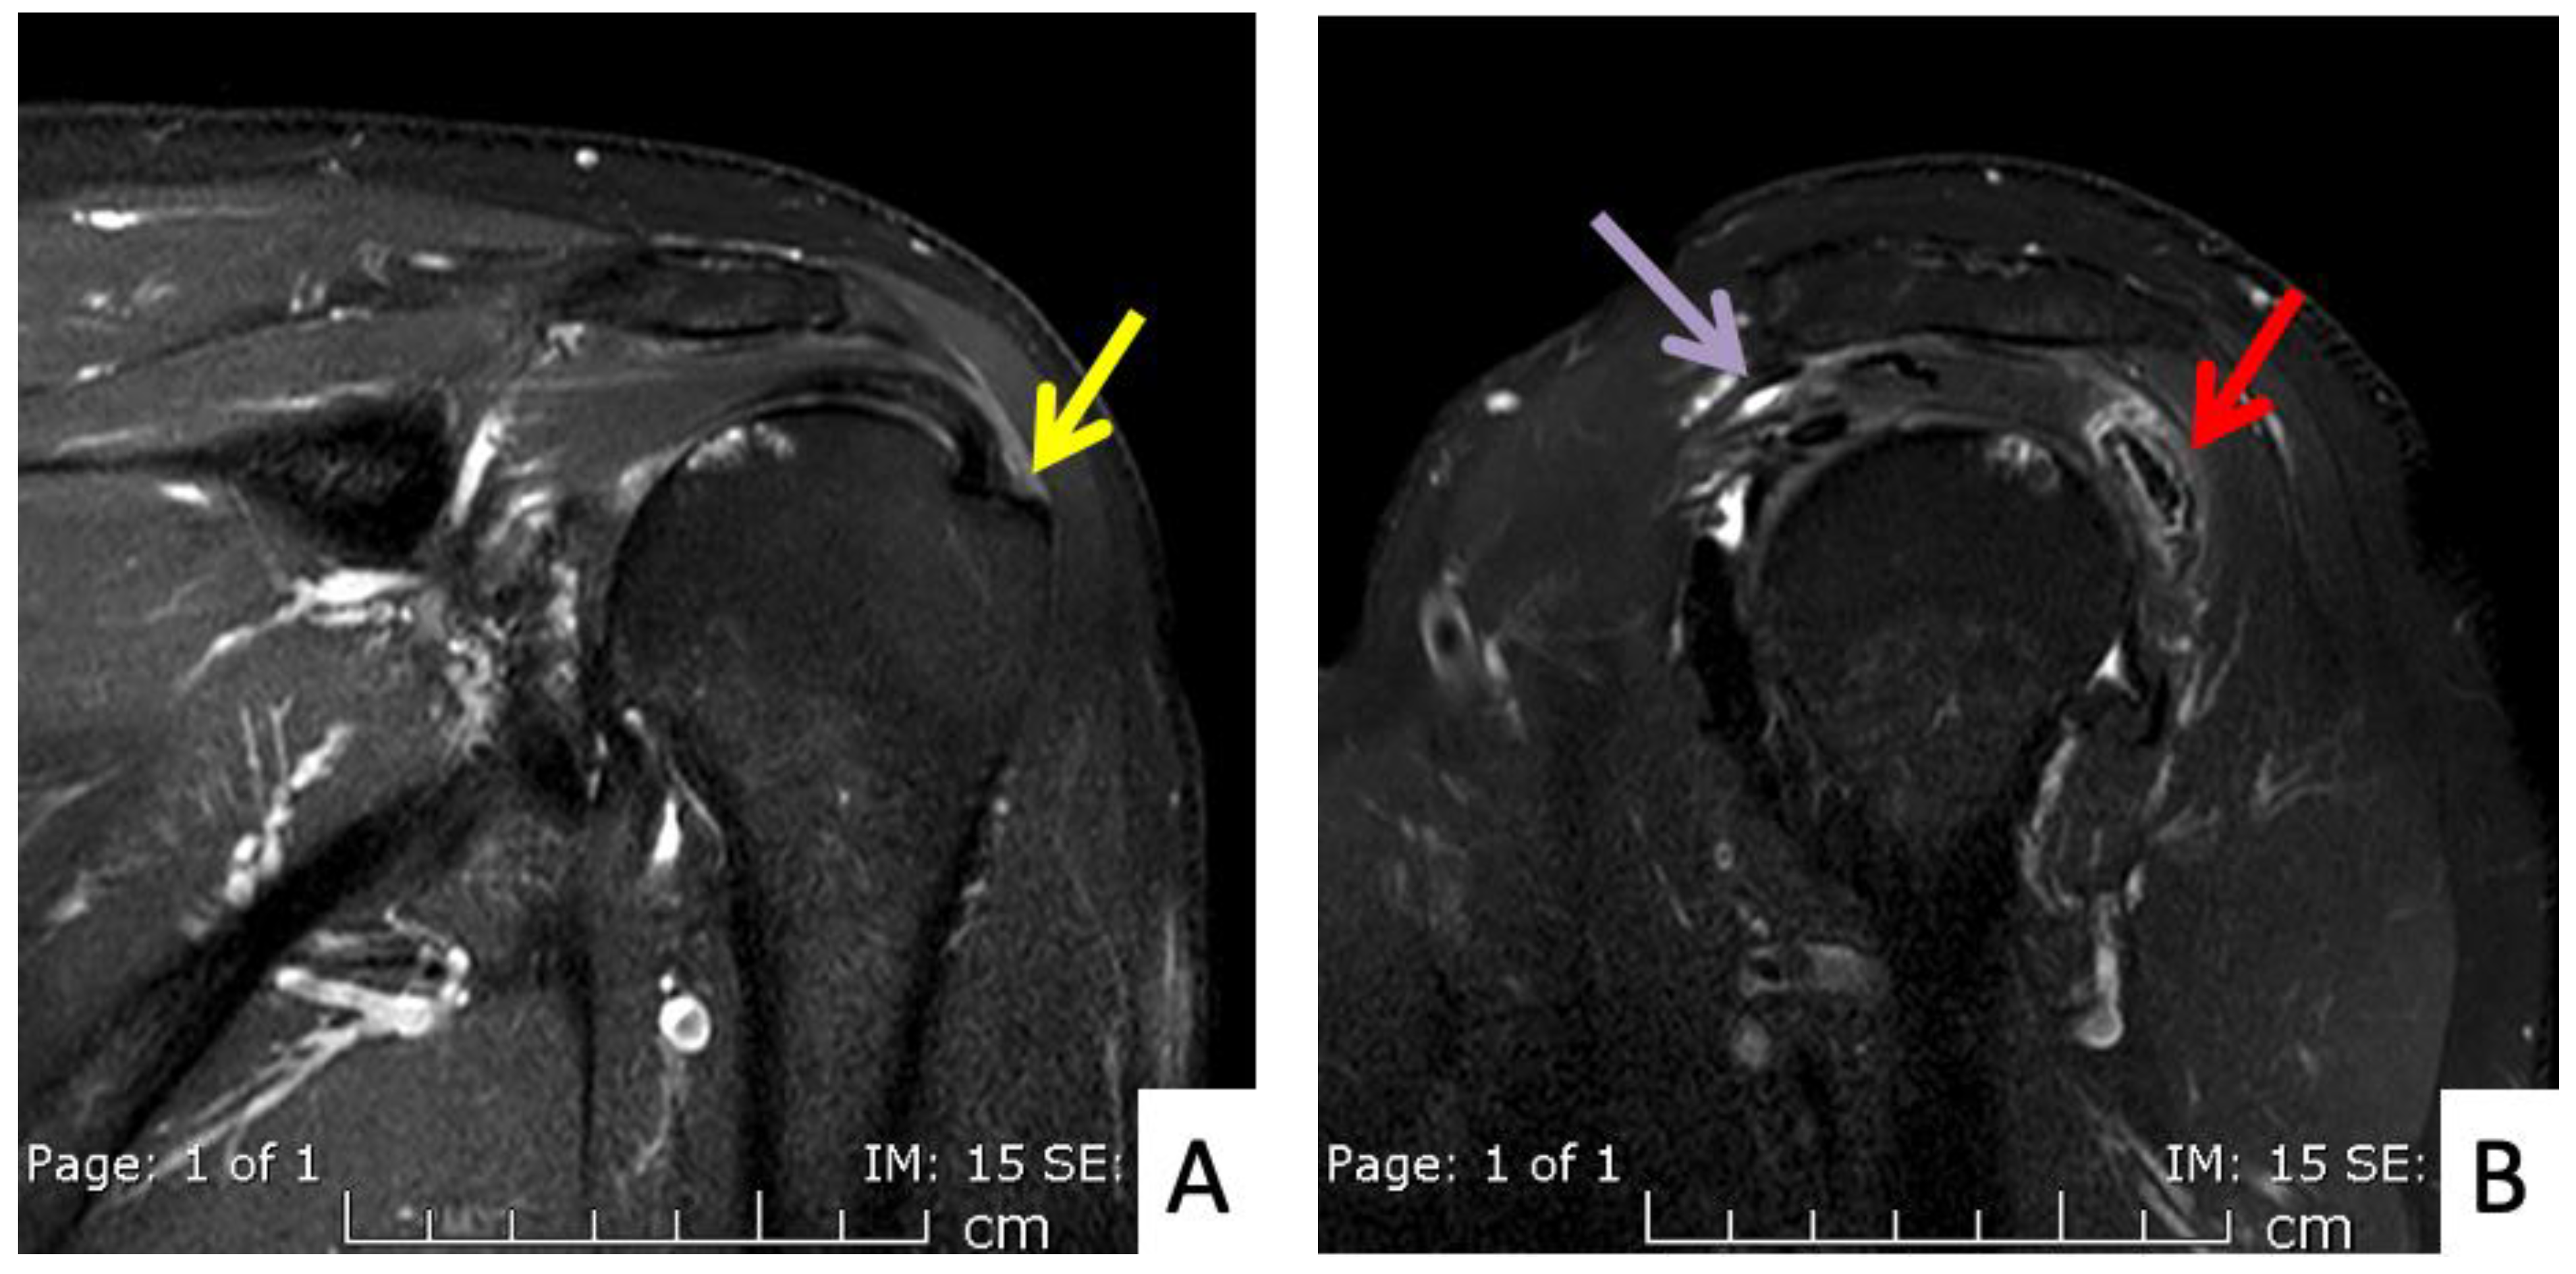

The fourth case was a 71-year-old Austrian male who began to feel left shoulder pain one day after a second dose of AstraZeneca vaccine. The injection was given with a 1.5-inch 25-gauge needle and the landmark was 1 fingerbreadth below the mid-lateral edge of the acromial process (Figure 2B). The needle direction was perpendicular to the skin. Right shoulder pain was the only symptom, as he had full range of shoulder motion. His pain did not improve after 6 weeks and he finally came to the orthopedic clinic. An MRI of his right shoulder showed a thin layer of subacromial-subcoracoid bursitis and a low-grade partial tear of the supraspinatous tendon (Figure 5A,B). He was given oral prednisolone (30 mg/day) for 10 days and his pain began to improve after 1 day with full return to normal activities in 2 weeks.

Figure 5.

MRI images of the left shoulder of Patient 4; (A) coronal and (B) sagittal T2-weighted images of the left shoulder reveal a small, partial-thickness, bursal surface tear at the footprint of the supraspinatous tendon (yellow arrow). Increased signal intensity of the myotendinous junction of the infraspinatous tendon indicates muscle strain (red arrow). An edematous subacromial bursa with thin fluid (purple arrow) was also observed.